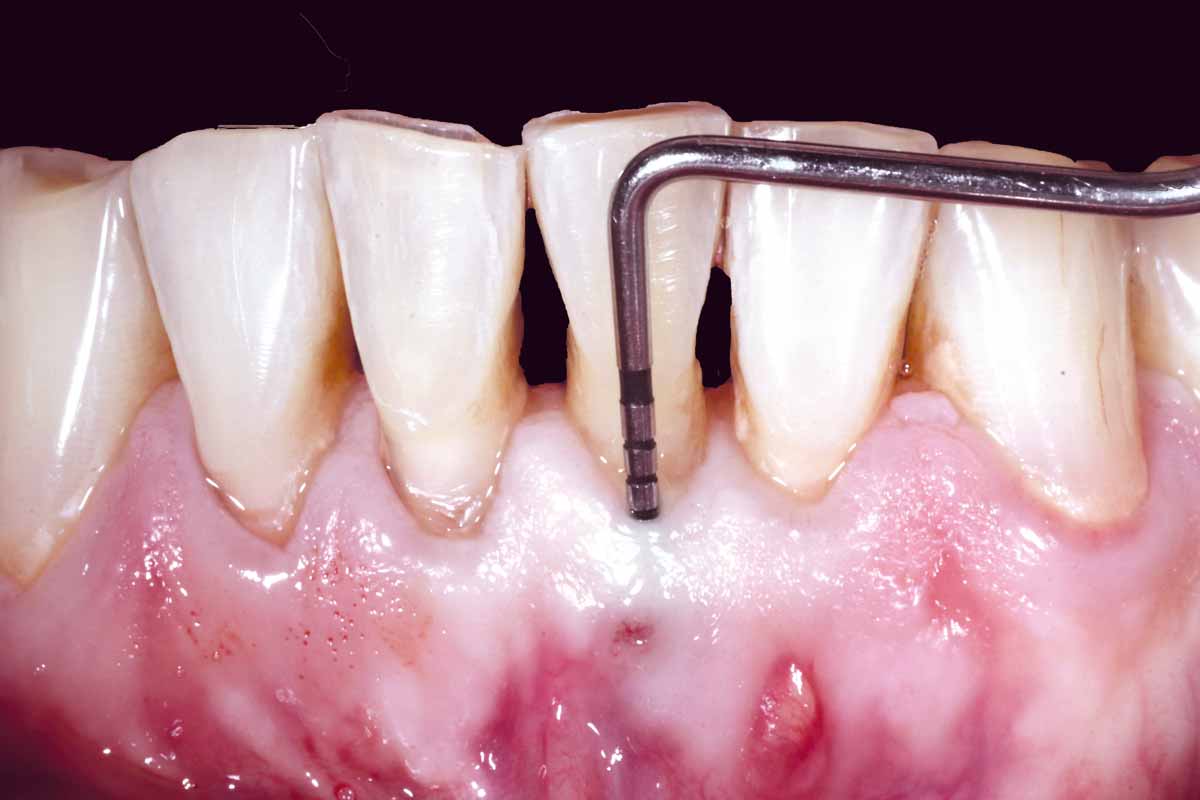

Pre-operative situation showing tooth 21 with deep periodontal pocket. Tooth presented with mobility grade III.